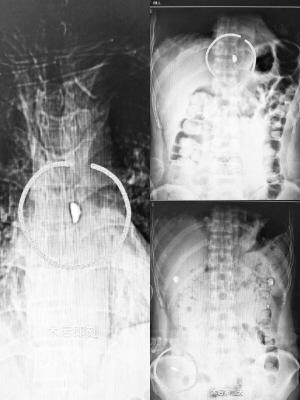

■术后拍摄的小铁块位置。(医院供图)

在给王先生手术的过程中医护人员发现,王先生气管、食管前后壁均见贯穿伤,于是,医护人员立即为王先生手术缝合修补气管、食管前后壁裂口。缝合修补后,下一步就是取出王先生体内的小铁块,但医护人员发现一站式术前检查锁定的铁块位置,在术中仔细探查时却不见踪迹,这是怎么回事呢?市三院心胸外科主任张东升凭借经验判断,王先生体内的小铁块极有可能神奇地被食管后方脊柱阻挡后,回落入食管腔内,并随着吞咽动作和食管的蠕动向胃肠道方向移位,已“逃离”手术区域。术中透视证实了张东升主任的判断。于是,医护人员决定就让小铁块在王先生体内再“漂一会儿”。

术后经过密切观察,小铁块随着食管以及整个消化道的蠕动,历经胃、小肠、大肠、直肠,于60小时后顺利“着陆”——排出王先生体外,最终完成了它的人体奇幻之旅。目前,王先生已经康复出院。